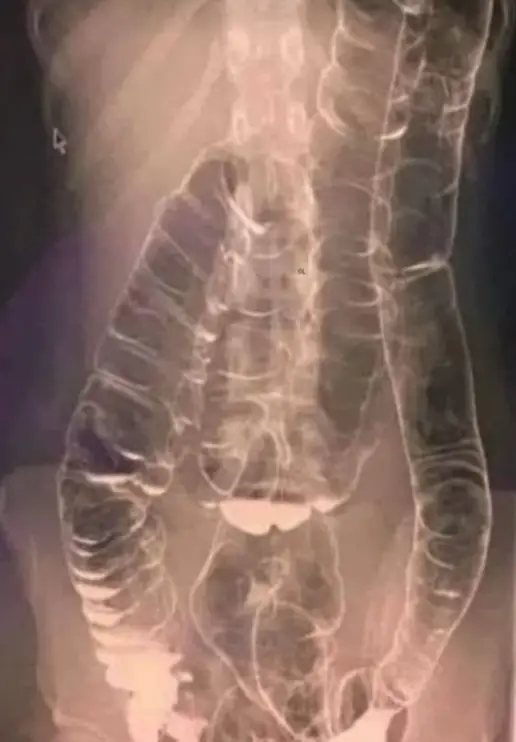

Orvosok egy röntgenfelvételen látták, mi történik, ha valaki két hétig nem tud rendesen üríteni. A felgyülemlett széklet miatt a vastagbél jelentősen kitágult, felfelé tolódott a mellkas irányába, a szív közelébe.

A hosszan tartó székrekedés miatt a bél redői, amelyek a működéshez szükségesek, ellapulhattak. Kezelés nélkül az ilyen állapot életveszélyes is lehet.